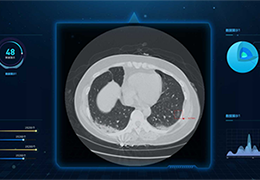

ART-Plan™ Artificial Intelligence Contouring